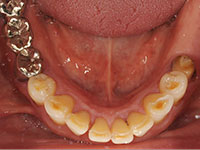

③下顎骨隆起

骨の防御反応によって下アゴにコブができています。